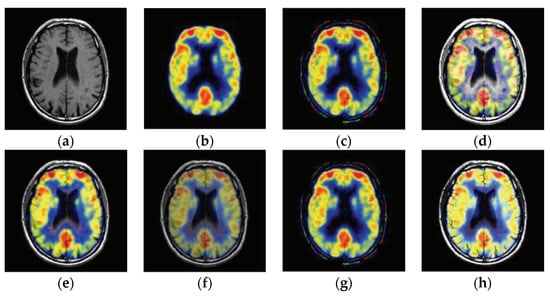

2.2. Proposed Fusion Strategy

2.2.1. Robust Edge Analysis

2.2.2. DLCNN-based Fusion Network